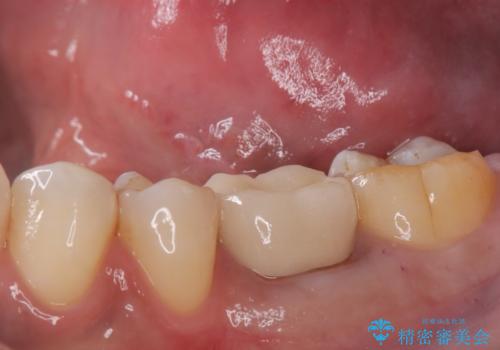

銀歯がとれた セラミックインレーで修復

- 銀歯が取れたとのことで来院されました。

拡大鏡下で丁寧に虫歯を取り除き、セラミックインレーによる修復治療を行いました。

銀歯を固着するセメントは経年劣化し溶け、隙間ができます。そこにプラークが侵入して虫歯が再発します。今回のように銀歯が脱離してしまうこともあります。

今回は銀歯が取れたので、虫歯が神経まで達して痛みが出る前に、強度・審美に優れ、虫歯の再発の少ないセラミックインレーにて治療を行うことができました。